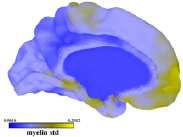

3.3 Methods Comparison

Figure 5 presents the L1 norm of B and C obtained for all our algorithm and datasets. Ten steps of refinement were conducted. At each step, five faces were subdivided and the algorithms run for ten optimization steps. Our results suggest that the tradeoff between the sparsity of B and C is different for the parameters selected. Because projected NMF do not control the sparsity of the loadings, PNMF basis tend to be very sparse but the projected loadings are not. The other factorization schemes balanced the L1 norms of B and C. For the parameters selected, the basis generated by dictionary learning were slightly sparser. We illustrate in figure 6 the results obtained when decomposing the myelin data using LE-PNNMF for a larger number of iterations. The basis obtained nicely decompose the map of large data variability into weakly overlapping components. The refinement had focused accordingly.